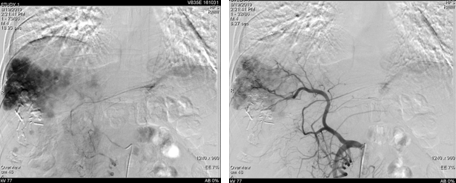

2018-12-11腹部CT检查提示,肝硬化、脾略大、门静脉高压;肝S6占位性病变,考虑原发性肝癌;肝S7段2枚结节;肝多发小囊肿,肝右叶钙化灶;双肾囊肿。

图片

图:腹部CT检查(2018-12-11)